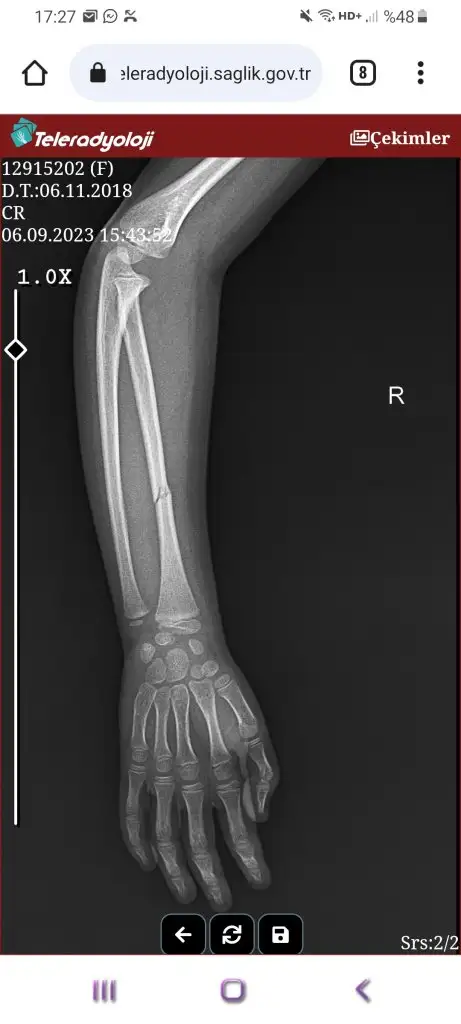

7 yaşındayken kolumu dört yerden kırmıştım kaydıraktan düşüp 1 ay kadar alçı kaldı sonra düzeldi. Bol ilikli kemik suyu tüketmiştim. Sadece kırılan yer seneler sonra bile soğukta sızlıyor bence. Bana öyle oluyor. Onun dışında kemiğim sağlam.Cok teşekkür ederim doktorda yasi küçük olduğu için sorun olmaz dedi ama anne yüreği işte bir türlü ikna olamiyorum